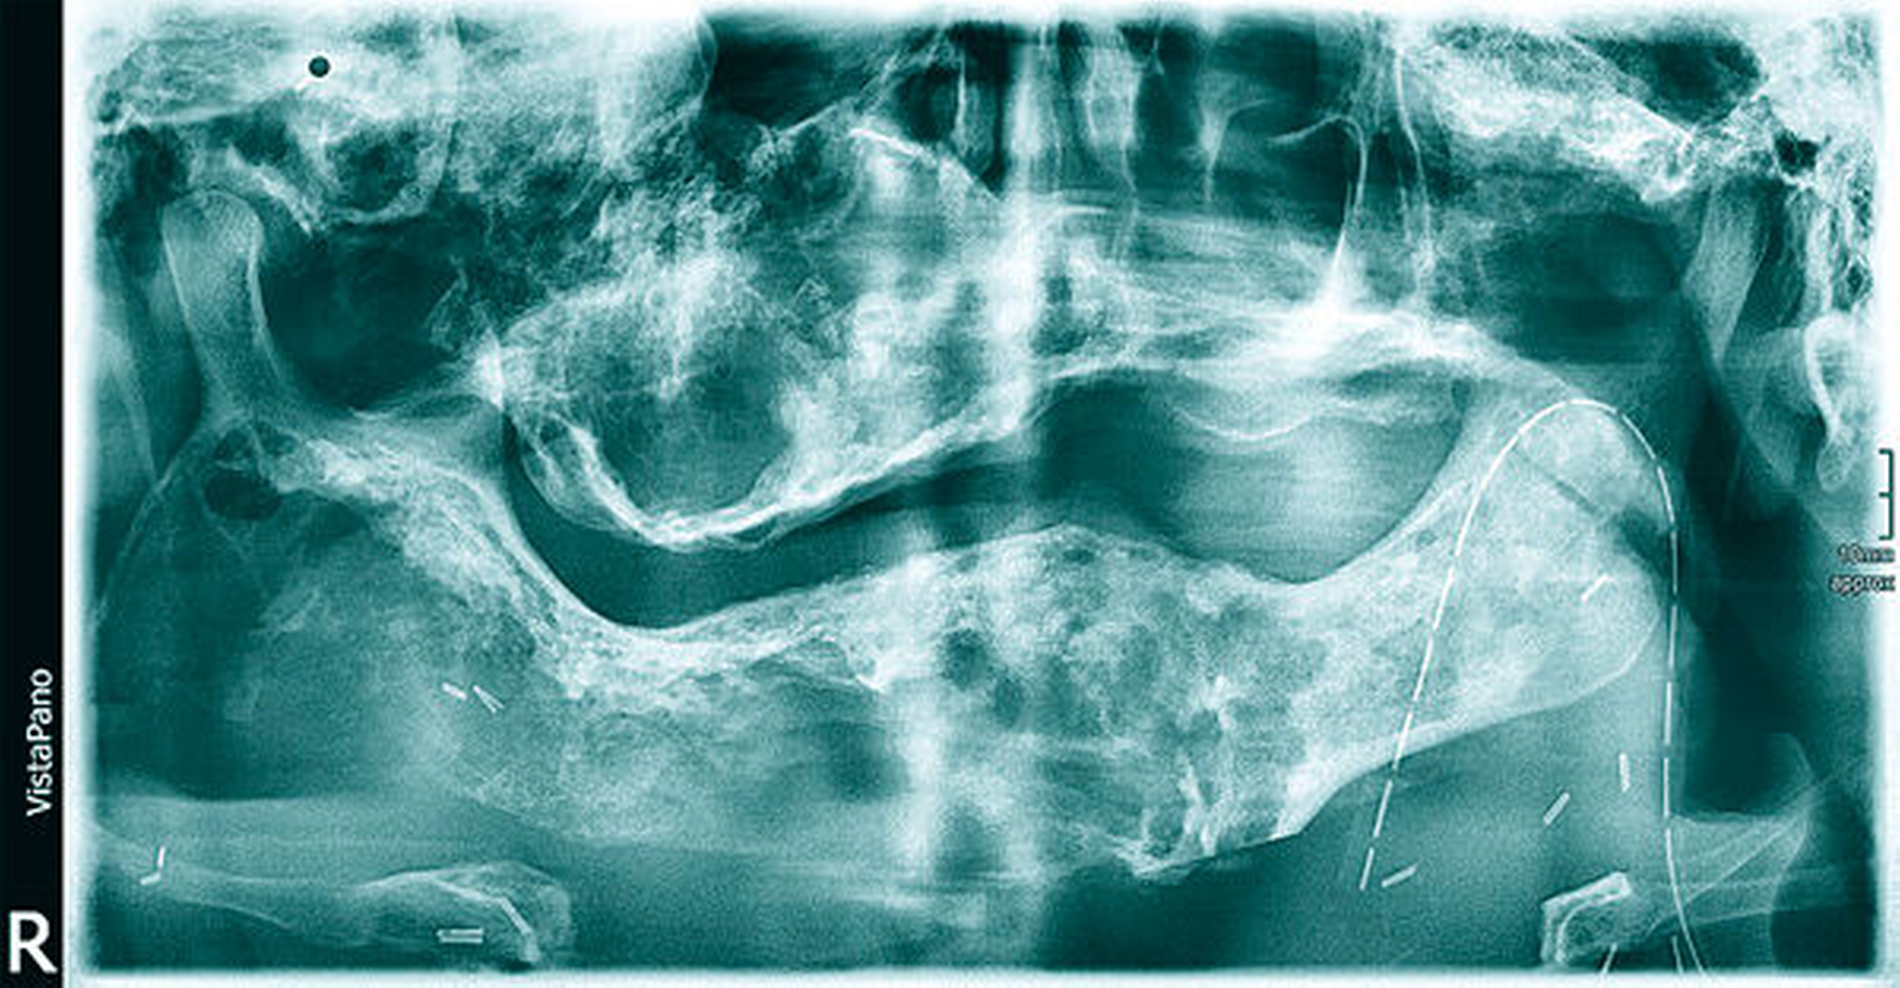

Klinisch zeigte sich eine circa 30 cm x 28 cm x 15 cm große, knochenharte und den Unterkiefer zu drei Vierteln umgreifende Raumforderung ohne Vincent-Symptomatik (Abbildung 1). In der Computertomografie zeigte sich eine inhomogene, blasige und hypodense Raumforderung mit Milchglasanteilen (Abbildung 2). Geplant wurde eine Abtragung der Veränderung mit Rekonturierung des Unterkiefers unter Verwendung eines statistischen 3-D-Formmodells, mit dessen Hilfe die ursprüngliche Form des Unterkiefers ermittelt wurde (Abbildung 3a). Im CAD/CAM-Verfahren wurden vier Resektionsschablonen hergestellt, um die geplante Osteotomie intraoperativ umzusetzen (Abbildung 3b).

Der histopathologische Befundbericht ergab ein über drei Kilogramm schweres Gewebe mit Anteilen einer teils spindelzelligen, teils locker fibrosierten und bekapselten Proliferation mit eingestreuten, teils trabekulierten Knochenbälkchen, teils mit angedeuteten Osteoblastensäumen sowie fokalen Osteoklastenlakunen und zentral demarkierter Osteolyse mit deutlich osteoklastärer Aktivität. In der Immunhistochemie zeigt sich anhand der Proliferationsfraktion (MIB-1) und der Anfärbung der Mitosefiguren (pHH3) ein niedriger Proliferationsindex (< 2 Prozent). Im postoperativ angefertigten DVT konnte der neu modellierte Unterkiefer mit seiner anatomisch korrekten Form gezeigt werden (Abbildung 6).